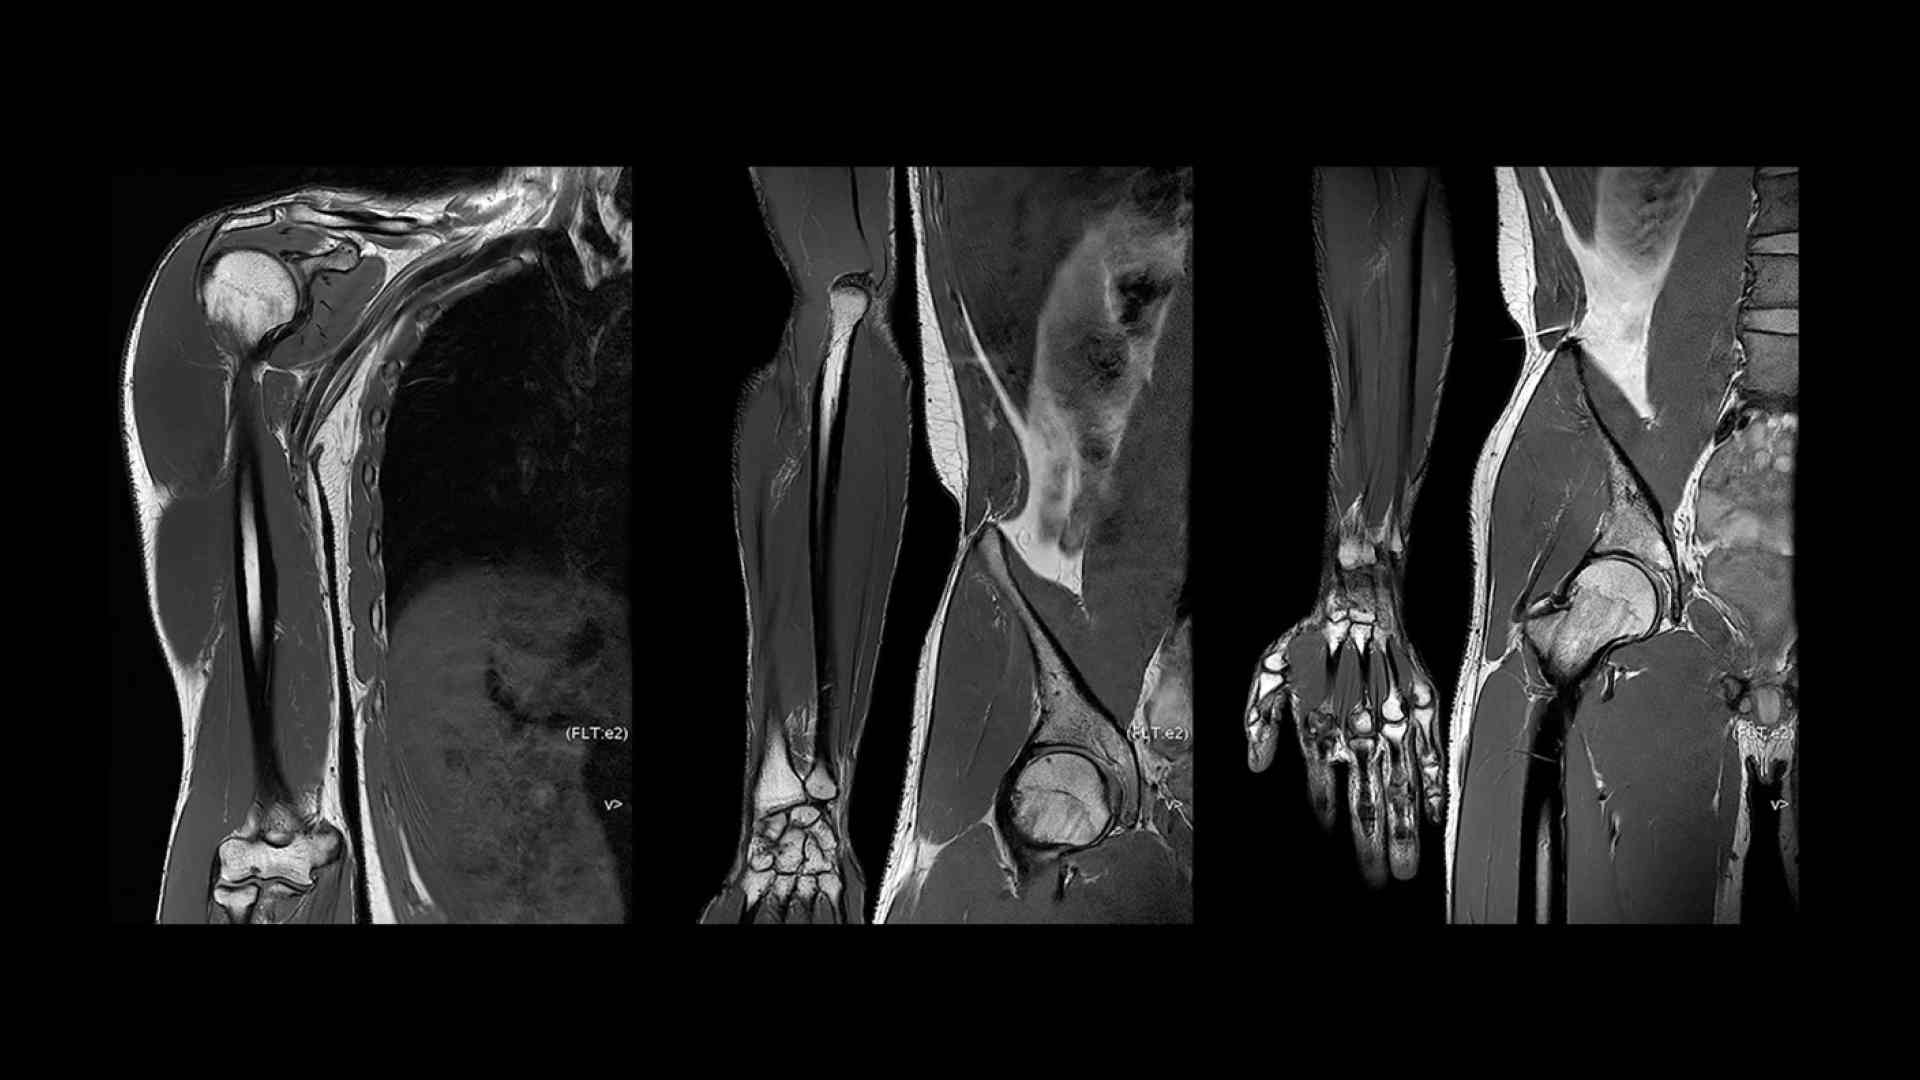

SIGNA™ Premier offers the versatility you need to fulfill all your clinical needs. Explore the advanced imaging and clinical capabilities achievable with the SIGNA™ Premier system.

Experience pin-sharp precision and remarkable speed with a 3T SIGNA™ Premier MRI scanner, coupled with AIR™ Recon DL and Sonic™ DL.

A powerful science tool with remarkable versatility

SIGNA™ Premier exemplifies many powerful robust attributes that makes it an exceptional MR for academic institutions. Alongside the SuperG gradients, which are proficient in executing the Human Connectome Protocol (HCP), the system has impeccable fMRI stability, a high RF-channel count with AIR™ Coils and a suite of deep learning applications.